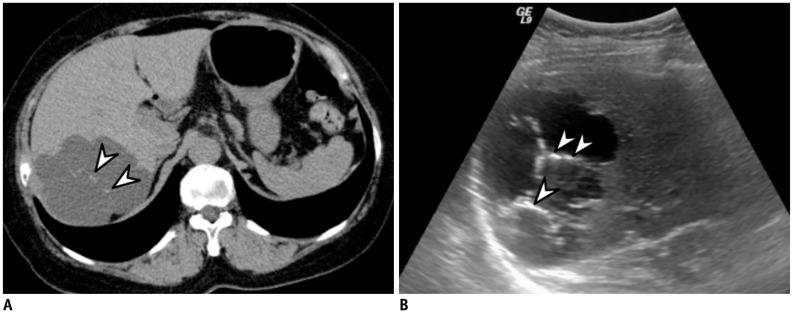

腹盆腔内肿瘤内钙化的影像学表现

Imaging Patterns of Intratumoral Calcification in the Abdominopelvic Cavity.

Intratumoral calcification is one of the most noticeable of radiologic findings. It facilitates detection and provides information important for correctly diagnosing tumors. In the abdominopelvic cavity, a wide variety of tumors have calcifications with various imaging features, though the majority of such calcifications are dystrophic in nature. In this article, we classify the imaging patterns of intratumoral calcification according to number, location, and morphology. Then, we describe commonly-encountered abdominopelvic tumors containing typical calcification patterns, focusing on their differentiable characteristics using the imaging patterns of intratumoral calcification.

摘要

肿瘤内钙化是最显著的放射学表现之一。它有助于肿瘤的检测,并为正确诊断肿瘤提供重要信息。在腹盆腔内,多种肿瘤会出现具有不同影像特征的钙化,不过此类钙化大多属于营养不良性钙化。在本文中,我们根据数量、位置和形态对肿瘤内钙化的影像模式进行分类。然后,我们描述含有典型钙化模式的常见腹盆腔肿瘤,重点介绍利用肿瘤内钙化的影像模式进行鉴别诊断的特征。